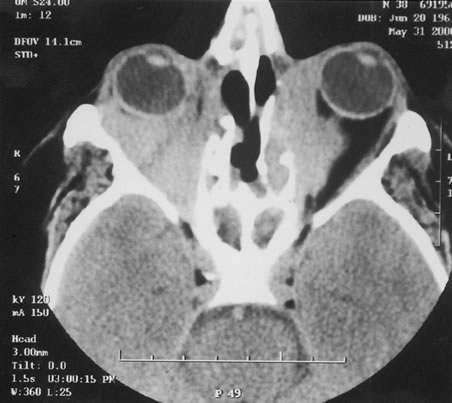

Even less common than retinopathy is lupus choroidopathy, of which only a few cases have been reported to date.214,224–226 Early autopsy studies demonstrated the frequent presence of mononuclear inflammatory cells in the choroid of patients with untreated SLE.208 The clinical changes seen in patients with lupus choroidopathy include serous elevation of the retina, most often of the neurosensory retina, serous elevations of the retinal pigment epithelium, and combined elevations of both (Fig. 7). These clinical findings are associated with systemic vascular disease, either hypertension because of lupus nephritis or systemic vasculitis.226 Treatment of the underlying disease, with systemic corticosteroids and immunosuppressive agents if needed, and control of any hypertension can resolve these serous retinal detachments.

Fig. 7. A. Fundus photograph and B. and C. fluorescein angiogram of a patient with choroidopathy and systemic lupus erythematosus. The fluorescein angiogram demonstrates multiple “smokestack” areas of fluorescein leakage. (Jabs DA, Hanneken A, Schachat AP, et al: Choroidopathy in systemic lupus erythematosus. Arch Ophthalmol 106:230, 1988. Copyright 1986, American Medical Association. Reprinted with permission.)